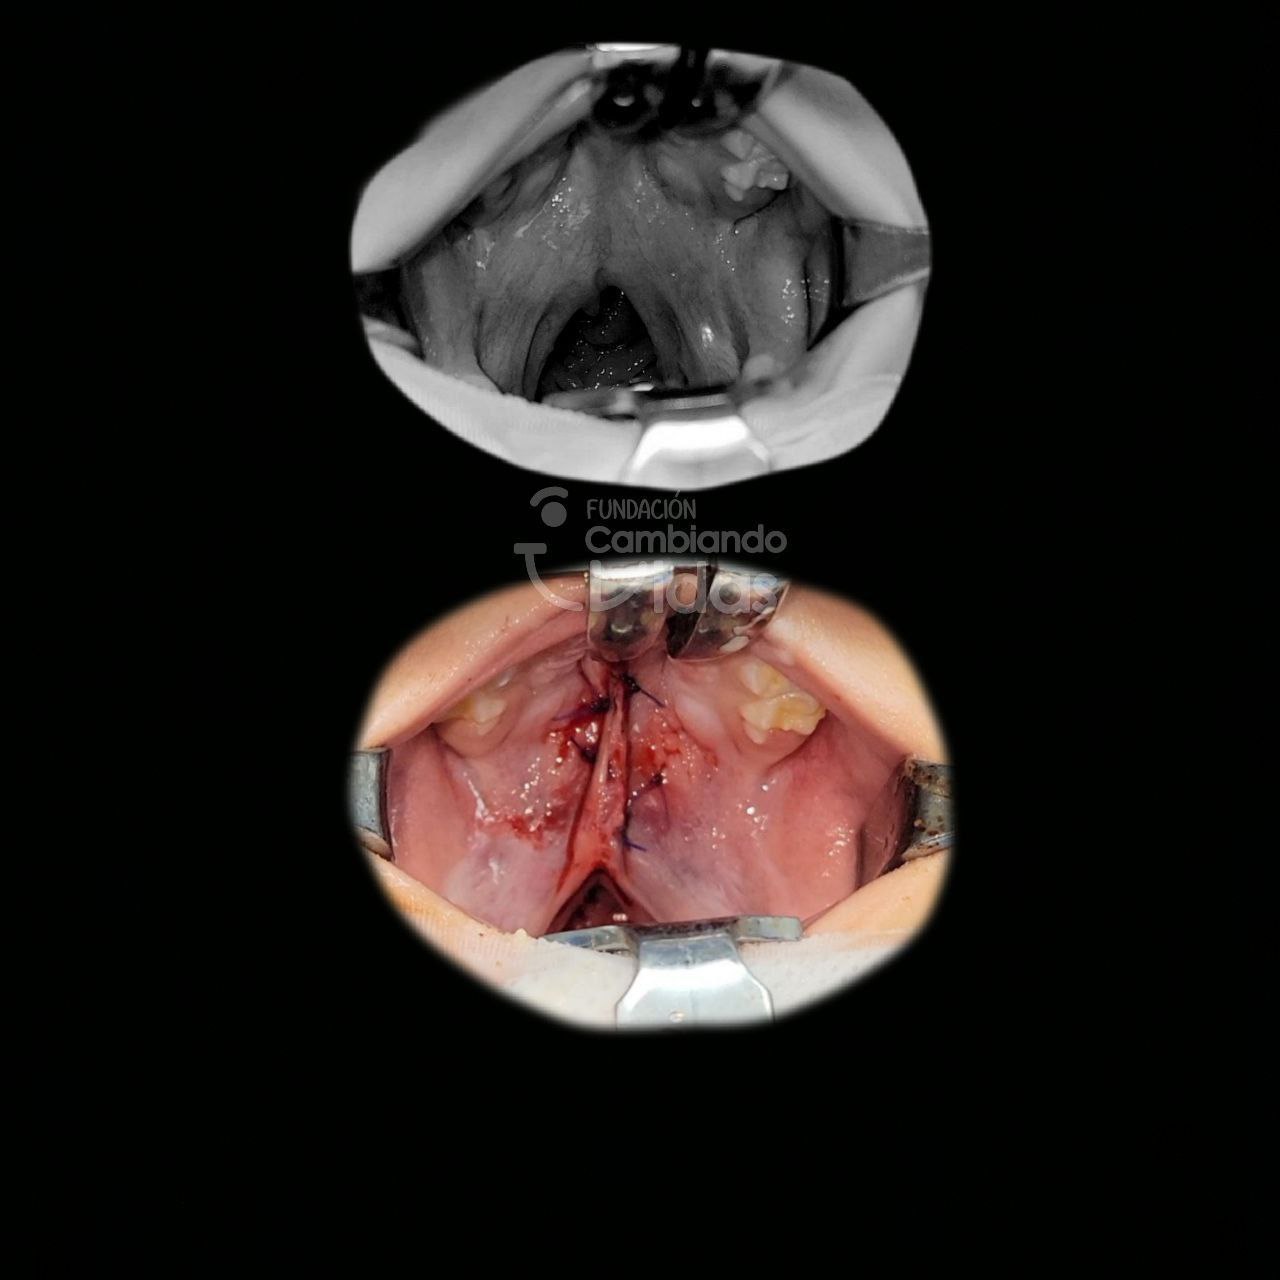

Leonel Caldera

Intervención Quirurgica: Palatoplastia Primaria